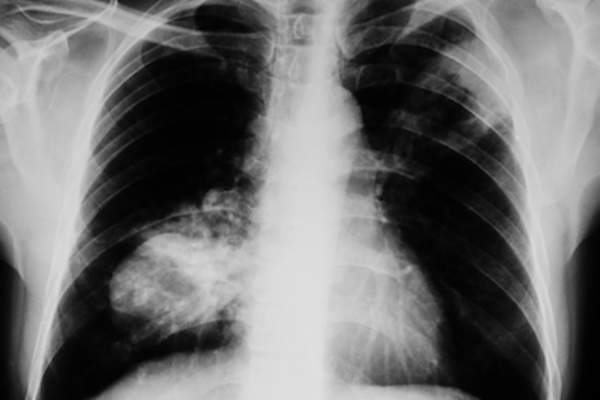

小细胞肺癌

小细胞肺癌(SCLC),通常被称为oat细胞癌,占肺癌的10- 15%Aemerican癌症协会。这些癌症扩散很快,但对化疗的反应比NSCLC更强烈,Lungcancer.org报告。

最具侵袭性的肺癌:小细胞肺癌

SCLC是肺癌的最进取的形式。它通常开始于在胸部和传播的中心,呼吸管迅速到身体的其他部位,包括大脑,肝脏和骨骼。